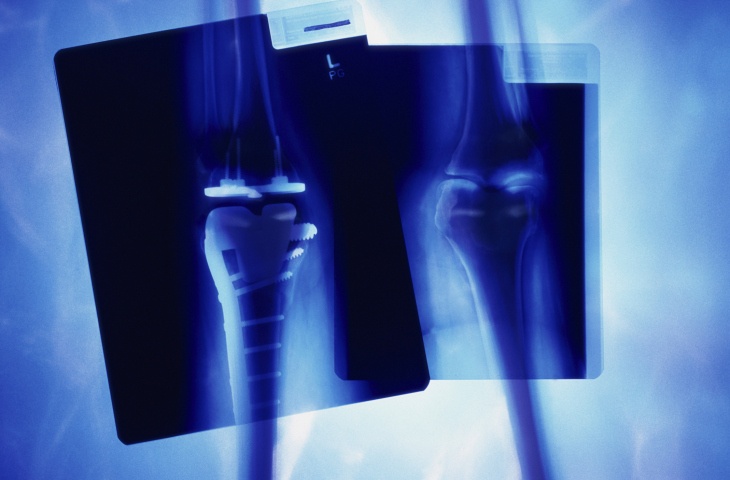

CMS plans to test the initiative at those hospitals—selected from 67 metropolitan statistical areas (MSAs) because of their widely varying costs for joint replacement—over the next 5 years, from April 1, 2016, through Dec. 31, 2020. Under CJR, participating hospitals will be held accountable for patient care from a hip or knee replacement procedure (the two most common inpatient surgeries for Medicare patients) through 90 days post-discharge.

Essentially, CJR puts hospitals in a risk-or-reward situation. Those that meet cost and care-quality standards (for patient satisfaction and fewer complications) will be rewarded with the highest CMS reimbursements for hip and knee replacements. Beginning in year 2 of CJR, however, hospitals that don’t meet these standards risk having to repay some of their CMS reimbursements.

These hospitals aren’t just responsible for the cost and quality of care within their own walls. CJR also holds them responsible for costs and patient care quality at any physician practices and rehab programs the patient uses post-discharge out through 90 days.